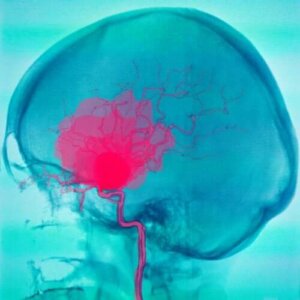

Subarachnoid blødninger er, hvor blod samler sig mellem arachnoid og pia. Blodet kommer som regel fra arterierne og kan have mange forskellige årsager. Det mest gængse er bristelsen af en aneurisme. De kan dog også have andre årsager.